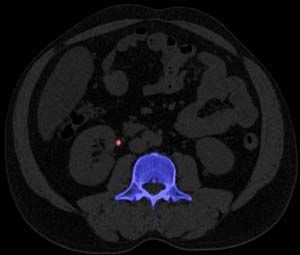

Fusion PET/CT detects an additional one-fifth of active lesions from the supraclavicular notch to the adrenals that are not found on chest CT alone, according to a retrospective study.